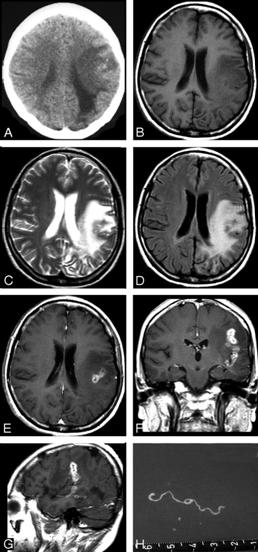

Bệnh ký sinh trùng sán nhái (Sparganosis) là nhiễm sán loại Diphyllobothrium hay ấu trùng plerocercoid larvae của giống Spirometra gồm có các loài như S. mansoni, S. ranarum, S. mansonoides và S. erinacei. Lần đầu tiên được mô tả ở Trung Quốc bởi Patrick Manson vào năm 1882 và ca bệnh đầu tiên ở người được báo cáo bởi tác giả Charles Wardell Stiles từ Florida, Mỹ vào năm 1908.

Một khi con người nhiễm, ấu trùng kết nang vô tính (plerocercoid larvae) di chuyển trong vị trí dưới da, ở đó chúng thường phát triển thành các nốt cục đau. Sự di chuyển của ấu trùng vào trong não dẫn đến bệnh sán nhái ở não (cerebral sparganosis), nếu di chuyển đến mắt dẫn đến bệnh sán nhái ở mắt (ocular sparganosis). Bệnh sán nhái lưu hành nhiều nhất ở Đông Á, mặc dù số ca đã được mô tả tại các quốc gia trên khắp thế giới, khoảng 300 ca được mô tả trên y văn đến cuối năm 2003 và hiện nay nhiều nước đã tổng hợp trong 15 năm qua con số cũng lên đến gần 1000 ca đến năm 2018. Chẩn đoán thường không đặt ra mãi đến khi ấu trùng sán nhái (sparganum larva) được phẩu tích lấy ra xác định. Praziquantel là thuốc được lựa chọn để điều trị sán nhái, mặc dù hiệu quả của thuốc vẫn chưa biết đầy đủ và phẩu thuật loại bỏ sán ra khỏi tổn thương nhìn chung là phương pháp điều trị tốt nhất. Các can thiệp y tế công cộng nên tập trung vào vệ sinh nguồn nước và thực phẩm, cũng như giáo dục sức khỏe về về bệnh tại các vùng nông thôn thường sử dụng nhái làm thuốc đắp (poultices).

Hình 1